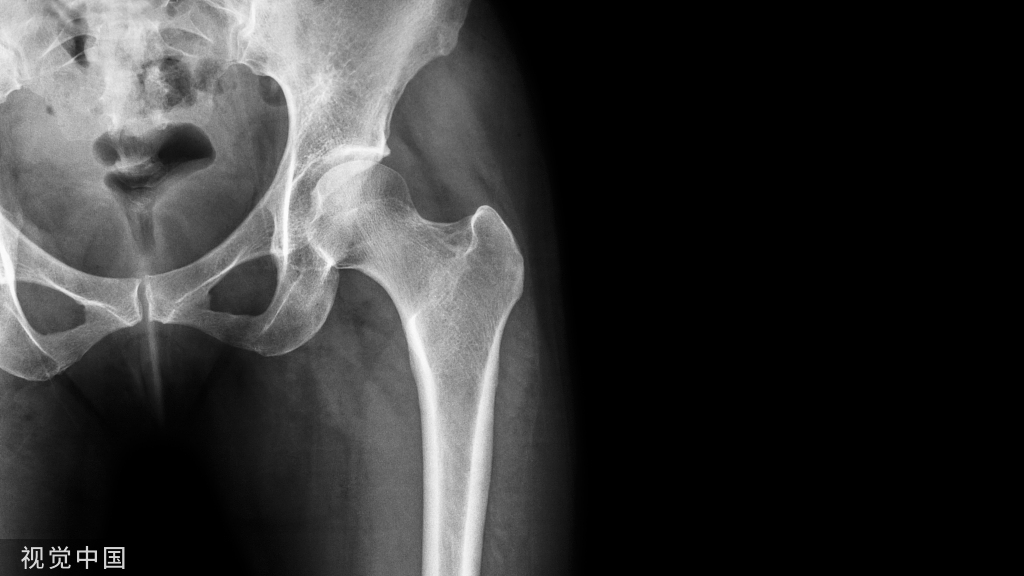

土耳其伊斯坦布尔xxx Baltalimani骨病医院的学者发现了一个脊柱严重角状后凸(≥90°)正位X线片的影像学征象,将其命名为 Baltalimani征

土耳其伊斯坦布尔xxx Baltalimani骨病医院的学者发现了一个脊柱严重角状后凸(≥90°)正位X线片的影像学征象,将其命名为 Baltalimani征。

Baltalimani征阳性:脊柱严重角状后凸(SAK)的顶椎相邻椎体处于垂直翻转状态。在正位x线片上可以观察到椎体轮廓呈轴位观。

Baltalimani征阳性的正侧位X片示例。这种严重成角压迫使得脊髓损伤发生几率比阴性征象增加了61.9%

相较于先天性脊柱后凸,脊柱结核和神经纤维瘤病患者所致脊柱后凸的病程进展更快,出现Baltalimani征时更易发生神经功能障碍。